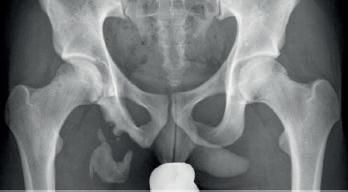

Fragility fractures of the pelvis, is een nieuwe term voor hetgeen we al vele jaren kennen als de pubistakfracturen bij ouderen.

De recente evolutie hierin is het inzicht dat ook deze fracturen dezelfde morbiditeit en mortaliteit met zich meebrengen als een heupfractuur. Bij patiënten die door pijn niet in staat zijn te mobiliseren kan een minimaal invasieve stabilisatie met percutane schroeven worden uitgevoerd (Fig. 3) Hoewel we op de klassieke radiografie vaak enkel de anterieure (pubistak) fracturen zien, is er vrijwel altijd ook een posterieure fractuur in het sacrum. Stabilisatie gebeurt daarom door een percutane sacro-ilacale schroef en door een schroef in de pubistak. Het doel van deze ingreep is steunname mogelijk maken, dit is dan ook steeds toegestaan postoperatief.

Fig. 2: Heupnagel Fig. 3: Percutane fixatie bekkenfractuur Fig. 1: Bipolaire heupprothese